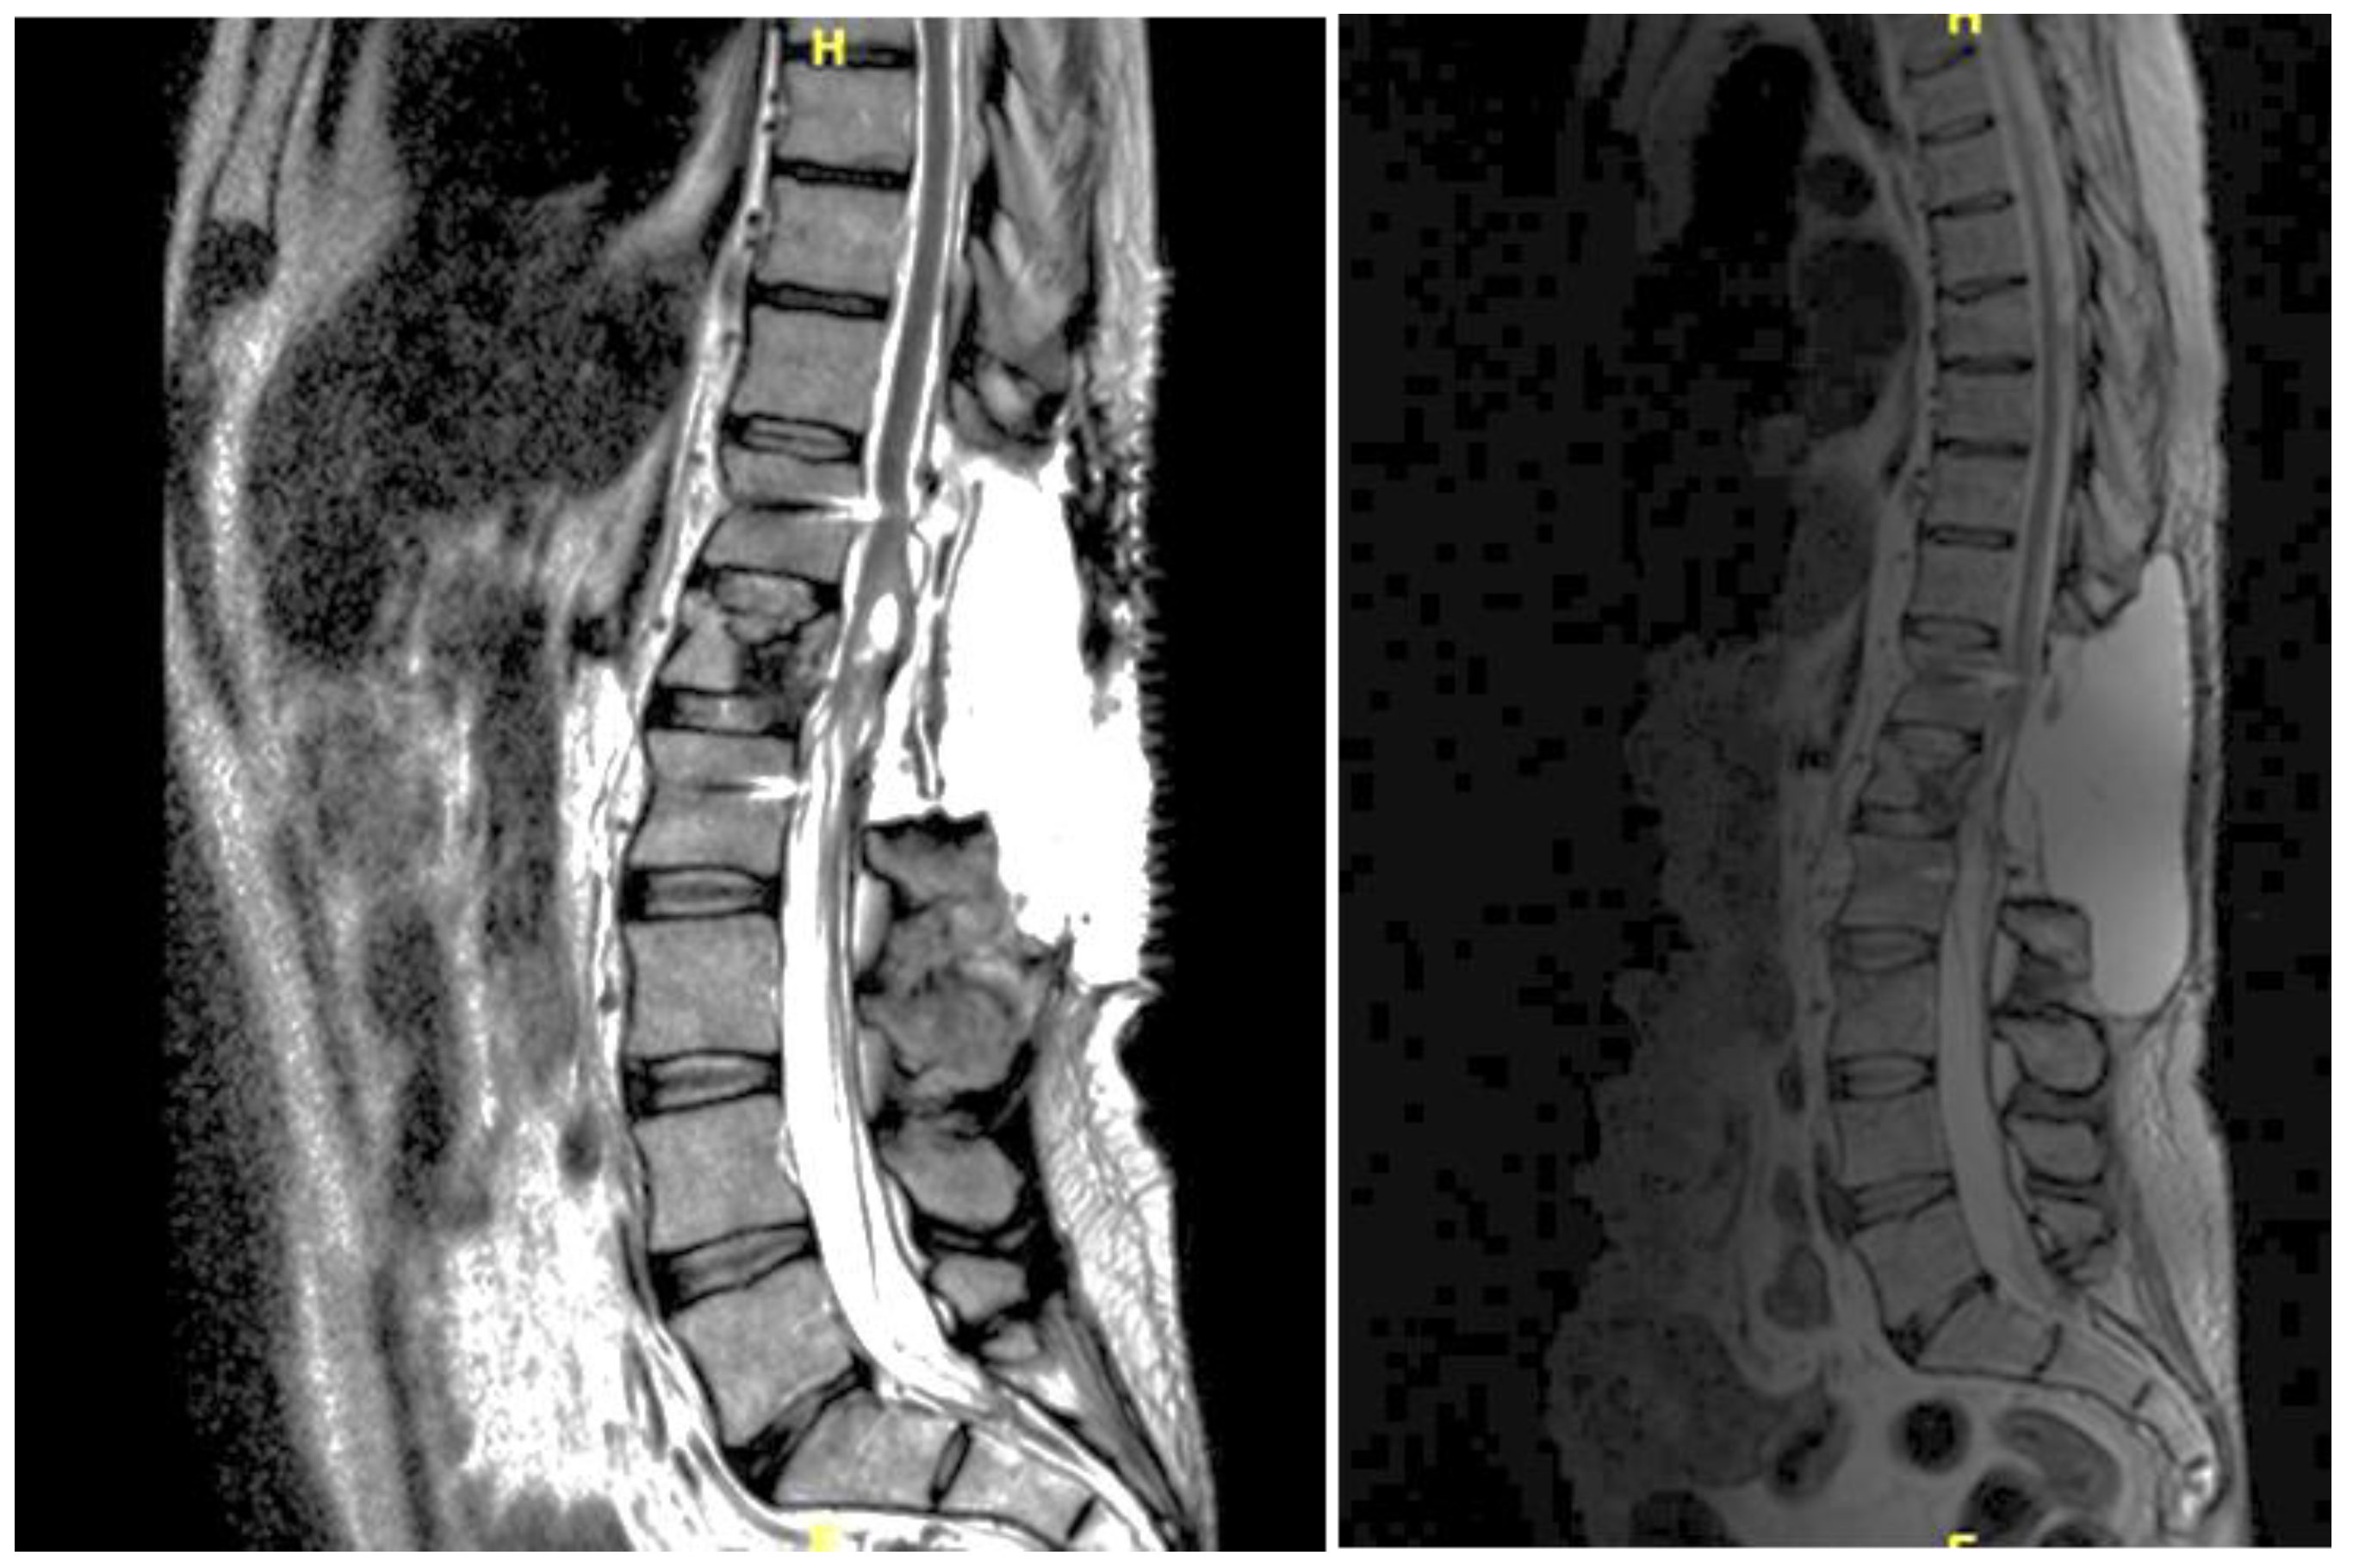

A 46-year-old man with a history of post traumatic burst fracture of L1 in a car accident, treated with lumbar fusion at D12-L2, developed seven months later lower limb weakness, sensory loss, and bladder and bowel dysfunction [Figure 1]. MRI revealed syringomyelia at D12-L2 compressing the conus medullaris. Initial surgery involved syrinx decompression through myelotomy, leading to significant symptom improvement. However, three months later, his symptoms recurred with an increased syrinx size. A second surgery introduced a syringo-subarachnoid shunt and removed scar adhesions, with temporary improvement although a post operative cerebrospinal fluid fistula occured. He underwent a third surgery with a syringo-peritoneal shunt, resolving the syrinx. Post-operatively, a follow-up MRI showed a significant reduction in the syrinx size and improvement in myelopathy: the patient’s neurological status improved, with gradual recovery of bladder and bowel functions.

Figure 1. Case 1: pre-operative MRI (left) and post-operative MRI (right).